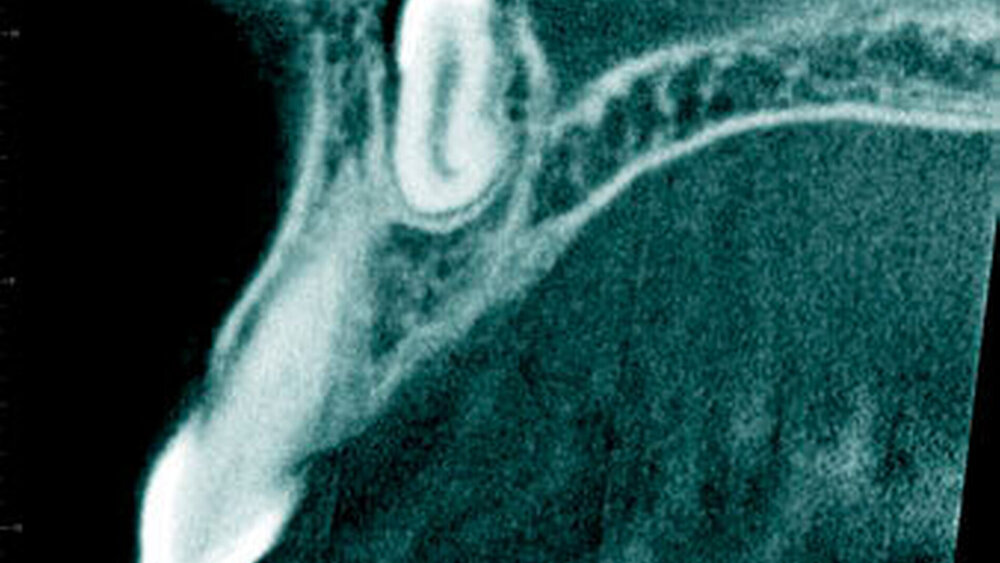

Eine Eruption des überzähligen Zahnes in die Nasenhöhle ist sehr selten [Primosch, 1981; von Arx, 1990; Stellzig et al., 1997; Rajab Hamdan, 2002]. Fallberichte werden jedoch immer wieder publiziert [Clementi et al., 2012; Krishnan et al., 2013; Mohebbi et al., 2013]. In einer großen Stichprobe waren 3,6 Prozent der überzähligen Zähne, meistens Mesiodentes, nach nasal durchgebrochen [Hyun et al. 2009] (Abbildung 20).